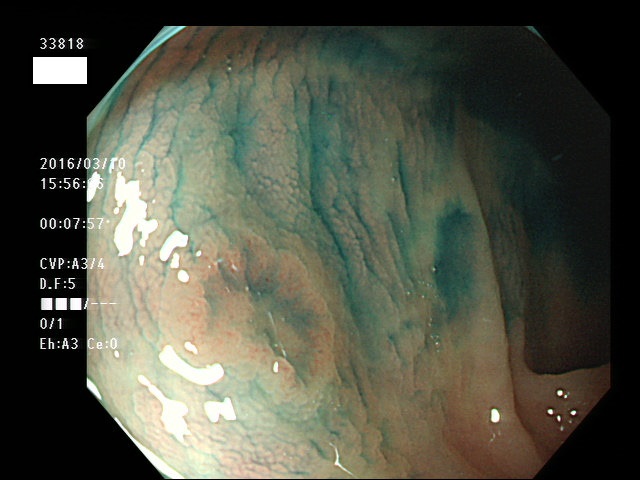

上記100名より抽出した平坦・陥凹型腺腫(=癌化の危険が高いが見落としやすい病変)の内視鏡写真